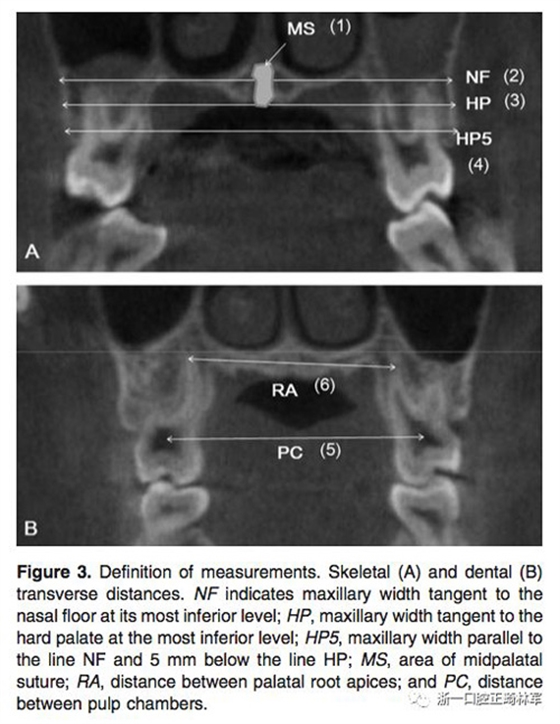

在治療前(T1)和擴(kuò)弓后3個(gè)月(T2)拍攝CBCT,獲得的數(shù)據(jù)由In Vivo Dental(Anatomage,San Jose,Calif)分析。為了在T1和T2階段設(shè)置相同的參考平面,CBCT圖像沿著腭中縫(x平面)定向,平行于腭平面(y平面)并且與鼻底(z平面)相切(Figure 2)。在腭中縫處評(píng)估橫向骨骼擴(kuò)張,并在三個(gè)不同的平面進(jìn)行線性測(cè)量:鼻底,硬腭和硬腭以下5mm。在根尖和牙冠水平測(cè)量橫向牙齒擴(kuò)張(Figure 3)。評(píng)估兩側(cè)的牙槽傾斜度,牙長(zhǎng)軸,牙齒垂直高度和骨開(kāi)裂等情況(Figure 4,5)。所有測(cè)量均在每個(gè)上頜前磨牙和磨牙區(qū)域進(jìn)行。